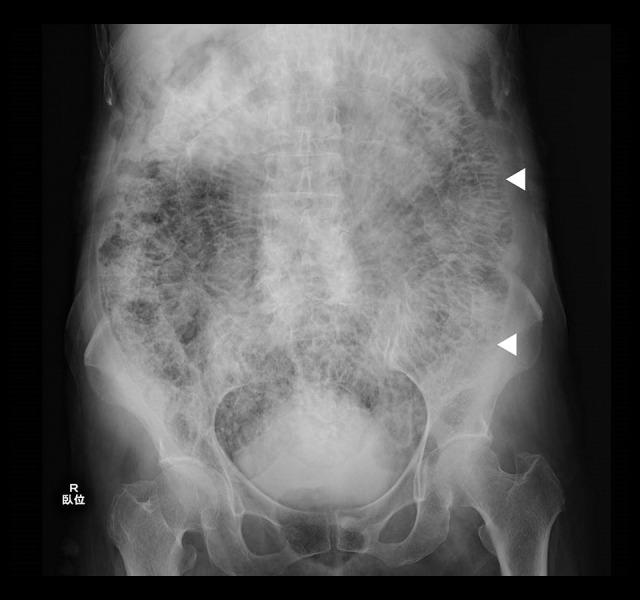

BACKGROUND Pneumatosis cystoides intestinalis (PCI) is a rare condition in which cystic gas is found in the submucosal and serosal tissues of the intestinal wall. CASE REPORT The patient, an 84-year-old woman, was referred to us because of abdominal distention and diarrhea lasting 2 weeks. On initial physical examination, there was marked abdominal distention without tenderness. Blood tests revealed no abnormalities, but simple abdominal radiographs showed gas in the small intestine. Contrast-enhanced computed tomography showed massive emphysema in the intestinal wall with no signs of portal gas or intestinal ischemia. The patient was diagnosed with PCI, and the prognosis was good. The patient showed improvement when managed with an elimination diet and follow-up. CONCLUSIONS Herein, we present the characteristics and diagnosis of PCI because the imaging findings of PCI can appear more severe than the actual condition, causing it to be mistaken for other serious diseases, which leads to unnecessary surgical procedures.

患者为 84 岁女性,因腹胀和腹泻持续 2 周而就诊。初次体格检查发现腹部明显膨隆,但无压痛。血液检查未见异常,但腹部平片显示小肠内有气体。增强 CT 显示肠壁广泛气肿,无门静脉积气或肠缺血迹象。患者被诊断为 PCI,预后良好。经饮食排除和随访治疗,患者症状改善。